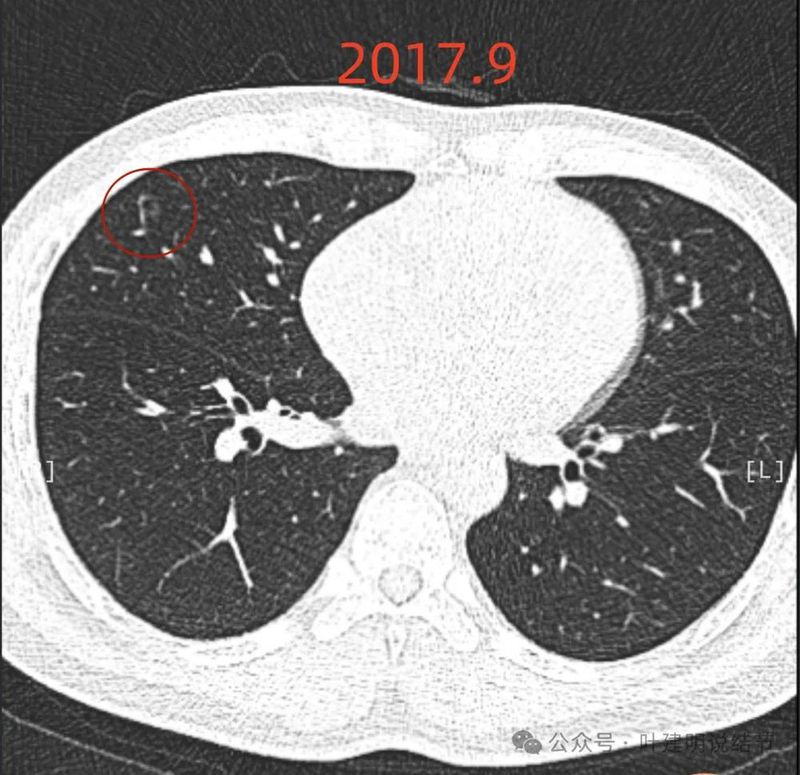

2017年初发现时,右中叶囊腔型病灶,囊壁密度淡但轮廓较清,有贴边血管,但血管无明显异常增粗,总体病灶较小,约1厘米光景或稍不到1厘米。整体轮廓是清楚的。